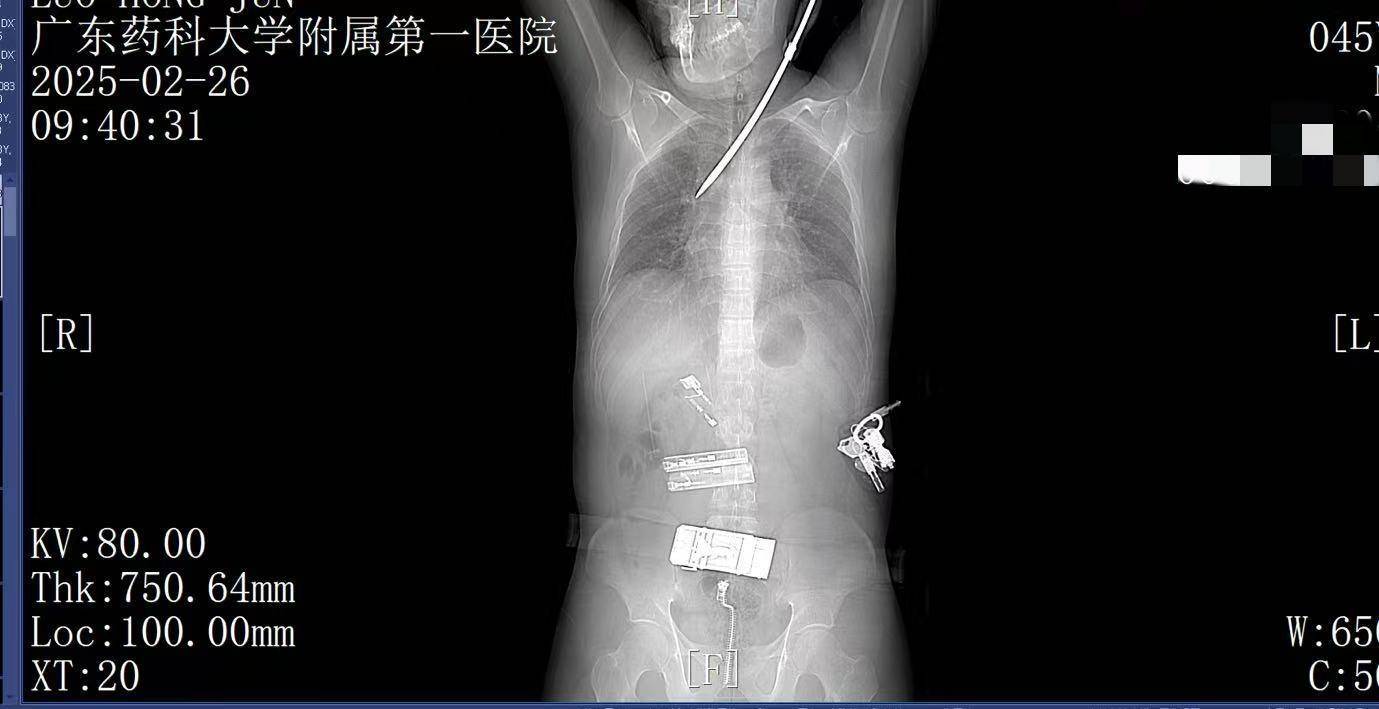

2月26日上午9时许,44岁的电梯工人罗师傅(化姓)正在广州某工地弯腰工作,突然一把螺丝刀从20多米高处坠落,刺中罗师傅的胸背部如何利用行业消息去炒币。罗师傅当即疼痛难忍,呼吸困难。工友立即呼叫120。一场惊心动魄的生死救援立即展开。

9:22,广东药科大学附属第一医院救护车到达现场,查看患者伤情后,黄业君主治医师立即固定好螺丝刀,避免再次移动损伤神经血管,并马上电话联系医院后方,医院急诊科主任曾育辉立即通知心胸外科、脊柱外科等相关科室紧急会诊如何利用行业消息去炒币。

9:39,救护车到达医院大门,院内急救团队已经做好准备如何利用行业消息去炒币。在紧密监护的情况下,全程采用绿色通道。到达医院时,罗师傅已经面色苍白,呼吸急促。螺丝刀已深深刺入罗师傅右肺,随时可能因大出血而危及生命。

9:41,快速完成头+胸+腹部CT检查,经多学科会诊,明确螺丝刀异物刺入肺部如何利用行业消息去炒币。CT显示螺丝刀紧贴肋间血管、上肺后段动脉,尖端距右肺门仅2厘米,一旦贸然拔出螺丝刀,极有可能引发大出血,导致失血性休克甚至死亡,必须紧急手术。

9:50,收入心胸外科急诊手术治疗如何利用行业消息去炒币。30分钟内即完成检查抢救处置。

无影灯下,麻醉科陈建颜主任团队精准实施单肺通气保障氧合,心胸外科肖海平主任团队沉着冷静,采用单孔胸腔镜技术进入胸腔,一步步地分离受损组织,仔细止血,避开重要血管如何利用行业消息去炒币。医护默契配合,成功将插入患者体内达13厘米的螺丝刀完整取出。手术顺利完成,罗师傅的生命体征逐渐恢复平稳,成功脱离了生命危险,大家心里悬着的石头终于落地。